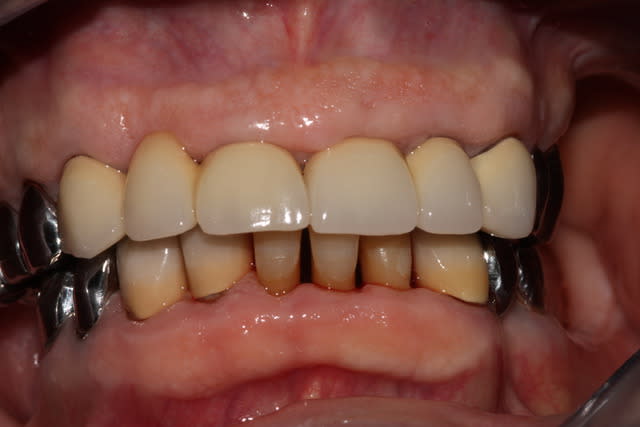

Ca c'est un boulot qui m'a fait extrêmement plaisir, parce que je trouve qu'on touche là à l'essence même de notre activité: permettre aux gens de manger.

Ce monsieur, 80 piges au compteur, est arrivé avec des vieilles provisoires, des gros compos, tout se cassait la figure... "Oh, mais à mon âge est-ce que ça vaut bien le coup de mettre des sous dans les dents..."

Pas de vraies difficultés techniques, pas de recherche esthétique marquée, du métal, on a reconstruit une occlusion de 5 à 5 seulement. Mais niveau qualité de vie, j'aimerai être toujours aussi efficace.

Photos un an après la pose. Pano avant.